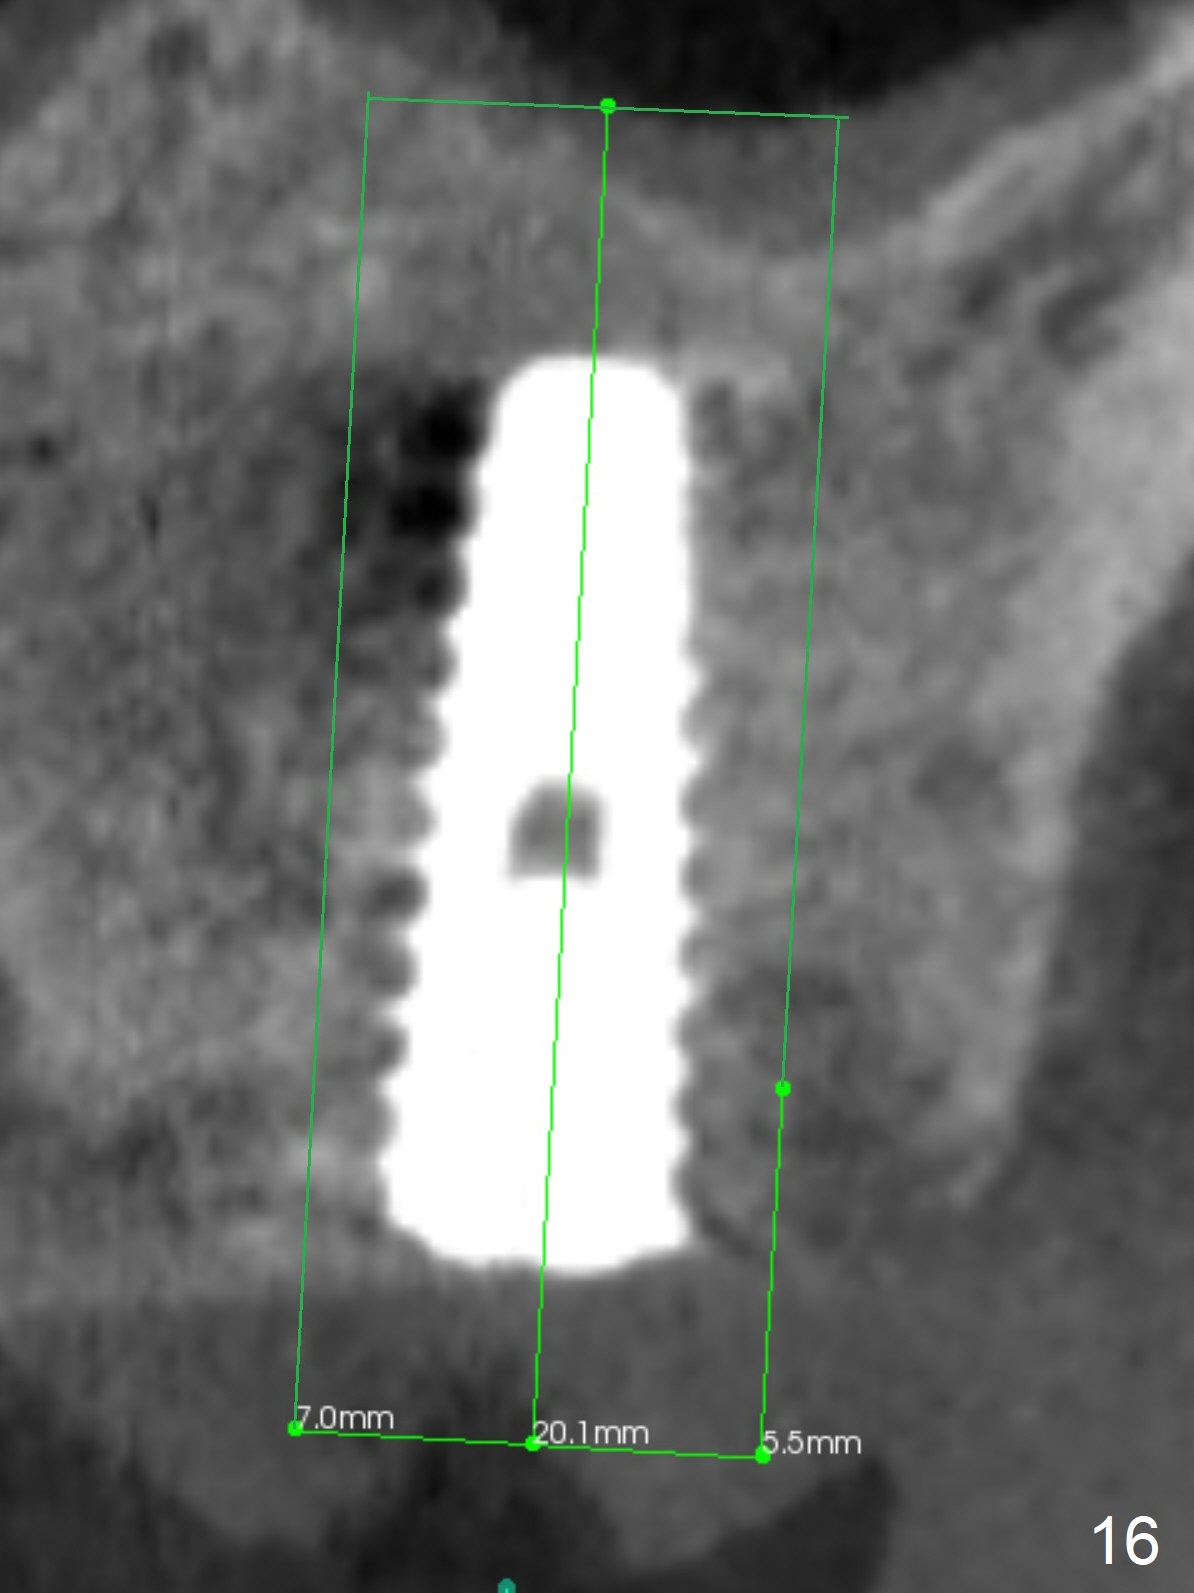

The amount of the bone graft mesial and distal the implant seems to reduce 3 and 4 months postop, respectively (Fig.6,7 arrowheads). When the acrylic is cut off 4 months postop, the bone graft is loose. The gingiva is unhealthy. The abutment and implant are loose. A healing abutment is placed (5x4 mm). The implant is torqued to 35 Ncm 6 months postop with the healing abutment reapplied. The patient will return for follow up nearly 9 months postop. A larger healing abutment will be used if the implant is stable. Two weeks later, use a smaller restorative abutment for easy impression. In fact the implant is unstable with #15 mesial shift due to abnormal occlusion with #17 (Fig.8). Bone density around the implant is low (* in Fig.9 (PA), 10,11 (CT sagittal, coronal sections)). A healing screw is placed for self healing. A 2nd option is to remove the implant (Fig.12), BEB (Fig.13) and place the implant deeper (Fig.14) or larger one (5.5-6.5x13 mm). The 3rd option is to place larger and longer implants (Fig.15 (tapered), 16 (cylindrical)). The implant access has partially closed 14 months postop, but there is a small buccal opening with sanguine exudate. Incision reveals severe bone loss around the implant; the mobile tooth #15 is extracted (Fig.17). After debridement and irrigation with normal saline, Vera Graft (Fig.18 *) and Collagen plug are placed with periodontal dressing.